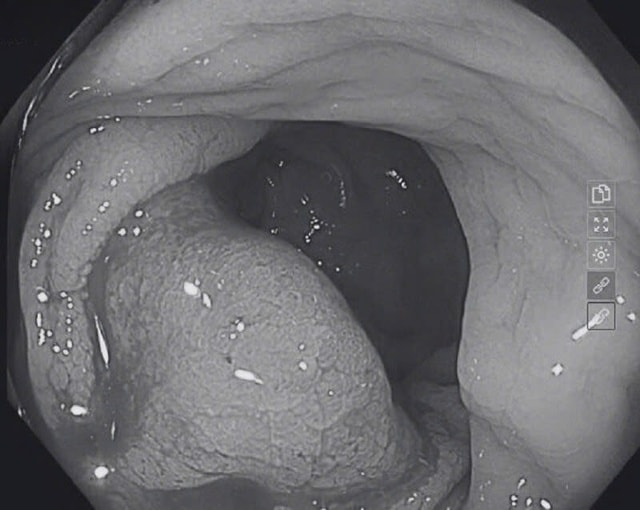

"Kết quả nội soi dạ dày phát hiện viêm thực quản trào ngược độ A, viêm teo dạ dày (C2) và theo dõi dị sản ruột. Nội soi đại trực tràng cho thấy tại đoạn đại tràng ngang xuống có nhiều polyp kích thước 0,3–0,8cm.

Đặc biệt, ở vị trí trực tràng, cách hậu môn khoảng 10cm, phát hiện một khối u chiếm khoảng 2/3 chu vi lòng đại tràng, kích thước gần 4cm, bề mặt cứng, dễ chảy máu khi chạm vào", BS. Quế nói.

Trước tổn thương nghi ngờ ung thư, bác sĩ đã tiến hành sinh thiết và làm mô bệnh học ngay trong quá trình nội soi. Kết quả xác định bệnh nhân mắc Carcinoma tuyến biệt hóa vừa một dạng ung thư biểu mô tuyến thường gặp ở đại trực tràng, kèm theo polyp đại tràng và trĩ nội độ I.